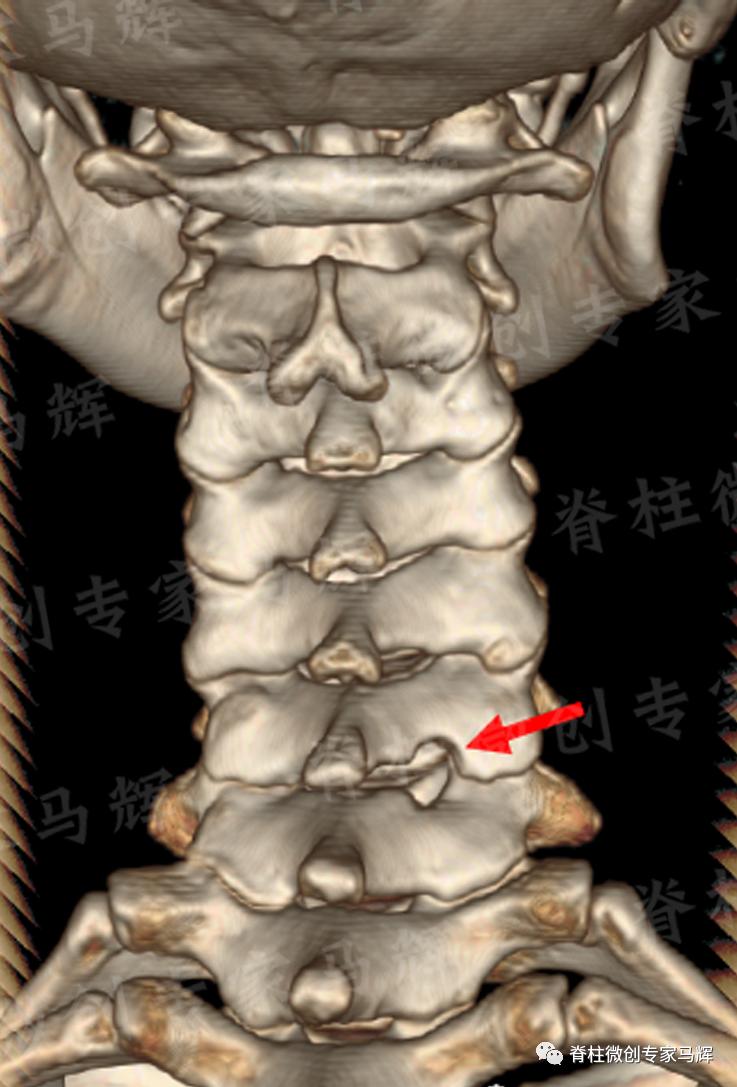

马主任仔细给患者做了检查,发现疼痛范围累及颈背部,及右上臂、前臂至手掌桡侧三指,无胸背部束带感,无行走不稳。根据影像学结果,诊断缪女士患6/7椎间盘突出症,属于神经根型颈椎病。

(术前)